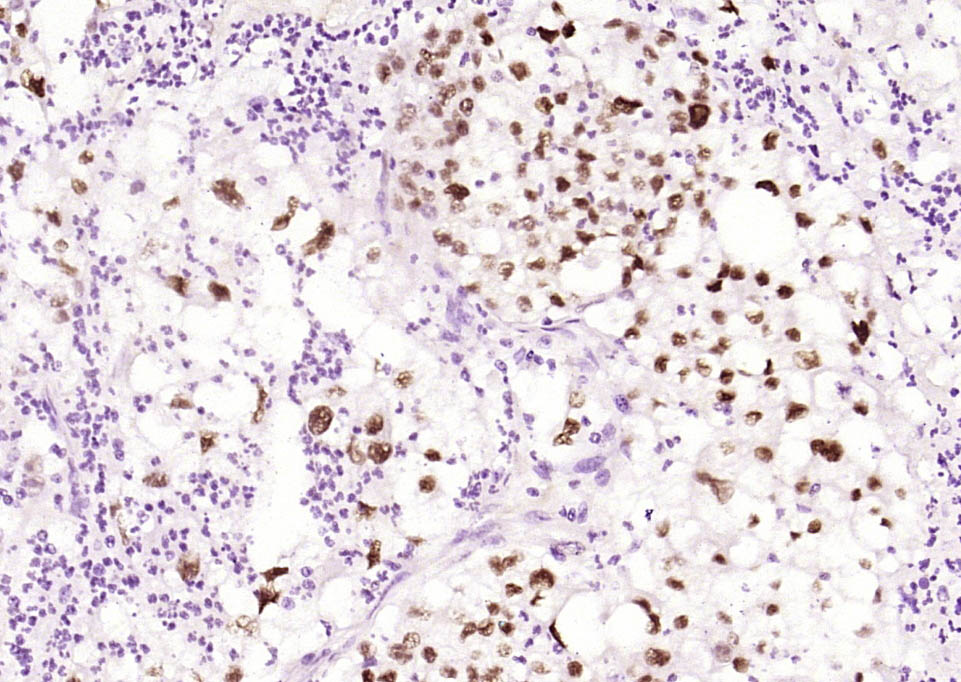

| IHC-P | Human, Mouse | Rat | 1:100-500 |